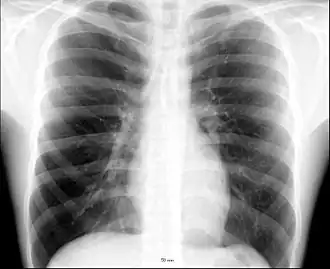

X-ray image of the human chest showing the internal anatomy of the rib cage, lungs and heart as well as the inferior thoracic border–made up of the diaphragm.

An X-ray of a human chest area, with some structures labeled

The contents of the thorax include the heart and lungs (and the thymus gland); the major and minor pectoral muscles, trapezius muscles, and neck muscle; and internal structures such as the diaphragm, the esophagus, the trachea, and a part of the sternum known as the xiphoid process. Arteries and veins are also contained – (aorta, superior vena cava, inferior vena cava and the pulmonary artery); bones (the shoulder socket containing the upper part of the humerus, the scapula, sternum, thoracic portion of the spine, collarbone, and the rib cage and floating ribs).